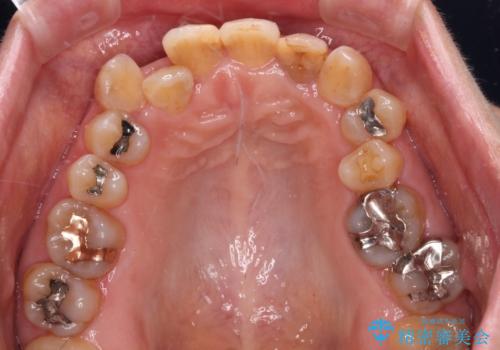

- 20年以上前に神経を取り除いた前歯の変色が気になるとのことで来院された患者様です。

レントゲン写真より、歯根の炎症が認められなかったため、ファイバーコアによる土台築製後、オールセラミッククラウンにて補綴することとしました。

また、真ん中の前歯はコンポジットレジンによる修復跡が目立っており、合わせてオールセラミッククラウンにて治療することとしました。